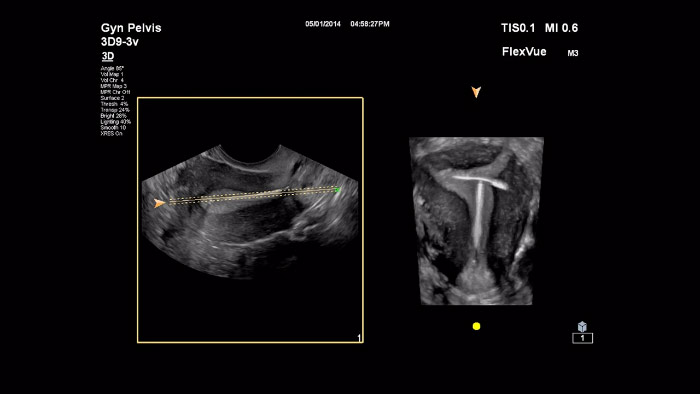

Philips FlexVue Demonstration by Dr Michael Ruma

En este vídeo, el Dr. Michael Ruma presenta FlexVue, una herramienta de evaluación 3D avanzada de Philips. FlexVue permite visualizar con facilidad vistas anatómicas difíciles desde un punto de vista técnico a partir de volúmenes 3D, esenciales para el diagnóstico de enfermedades obstétricas/ginecológicas.

Philips MPR Touch Demonstration by Dr Michael Ruma

En este vídeo se describe MPR Touch, una función más intuitiva que los controles de MPR tradicionales. A diferencia de los mecanismos empleados para manipular un conjunto de datos de volumen de la MPR tradicional, MPR Touch permite realizar movimientos sencillos en la pantalla táctil para manipular todos los parámetros multiplanares y así producir la presentación de volumen 3D deseada.